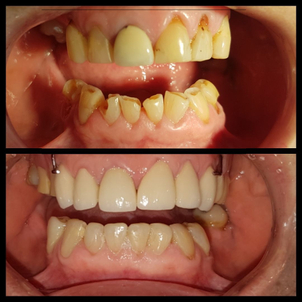

Paciente tratada por la Dra. Claudia Mora Pérez

Como lo señala la Clínica Mayo, después de una endodoncia, el diente restaurado con la nueva corona puede volver a funcionar con normalidad y lograr una buena estética. No obstante, aún siendo uno de los mejores tratamientos para salvar un diente cariado y muy infectado, se desaconseja en determinadas circunstancias clínicas que fuerzan al paciente a recurrir a otras opciones como la implantología dental. Algunos casos a valorar son:

A su vez, es importante que el médico cuente con un historial clínico del paciente que le permita saber si el tratamiento de endodoncia es compatible con alguna otra condición de salud. Tal es el case de: